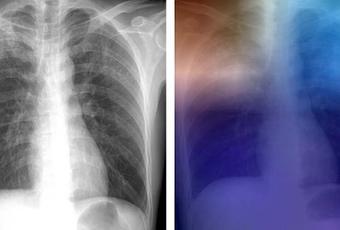

Un modèle qui peut atteindre 99% de précision : un modèle réalisé à partir de 1.007 images de patients avec et sans tuberculose active apportant de multiples jeux de données de radiographie thoracique a permis aux chercheurs de développer plusieurs modèles d'apprentissage approfondis qui testés sur 150 cas ne sont en désaccord avec le diagnostic radiologique humain que dans 13 cas seulement. Avec la participation (réduite ou à distance) d'un expert humain, la précision nette du modèle atteint près de 99%. L'exemple est donné ici avec l'image couleur ci-contre : les zones rouges et bleu clair dans les lobes supérieurs représentent les zones activées par le réseau neuronal profond de " l'intelligence artificielle " . Le réseau se concentre ainsi sur des parties de l'image où la maladie est présente (les deux lobes supérieurs).

Avril, 2017 Deep Learning at Chest Radiography: Automated Classification of Pulmonary Tuberculosis by Using Convolutional Neural Networks (Visuel@Radiological Society of North America)